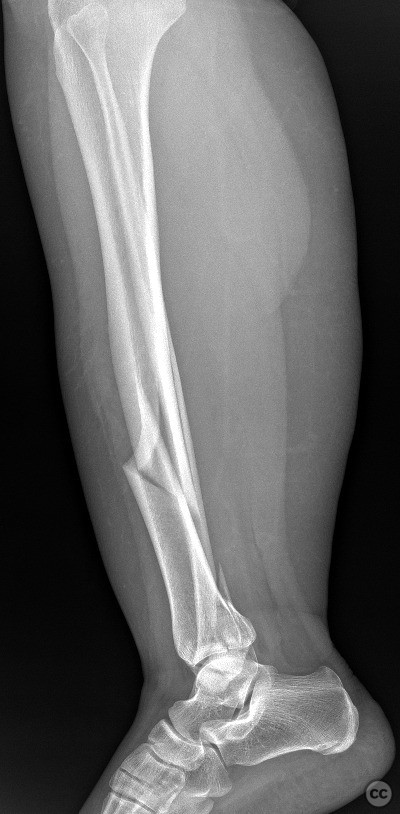

Clinical and radiological findings:  A 45-year-old male sustained a high-energy trauma resulting in an ipsilateral closed tibial shaft fracture and a trimalleolar fracture of the ankle. Initial radiographs demonstrated a displaced mid-diaphyseal tibial fracture (AO/OTA 42-A3) and a trimalleolar ankle fracture (AO/OTA 44-C1), with involvement of the medial malleolus, lateral malleolus, and posterior malleolus. No evidence of open injury or neurovascular compromise was present on examination.